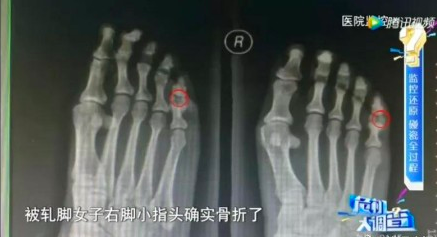

这时候女子趁司机不注意将脚伸向了车轮胎,制造被碾压的假象(送往医院后发现脚趾确实骨折了,但事后经调查查明她是事前用木槌砸断自己的脚趾)。